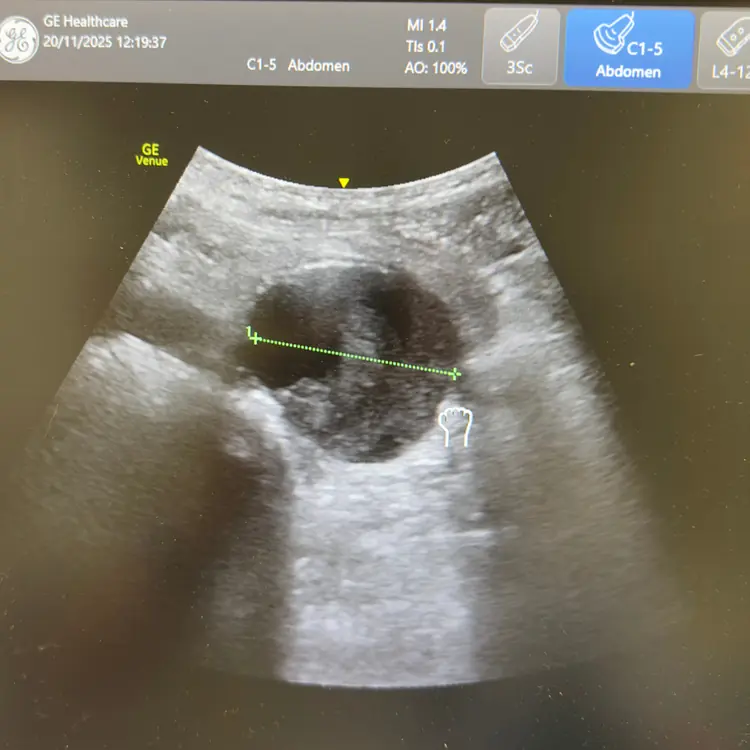

Voir lâaorte avant quâelle ne cĂšde.